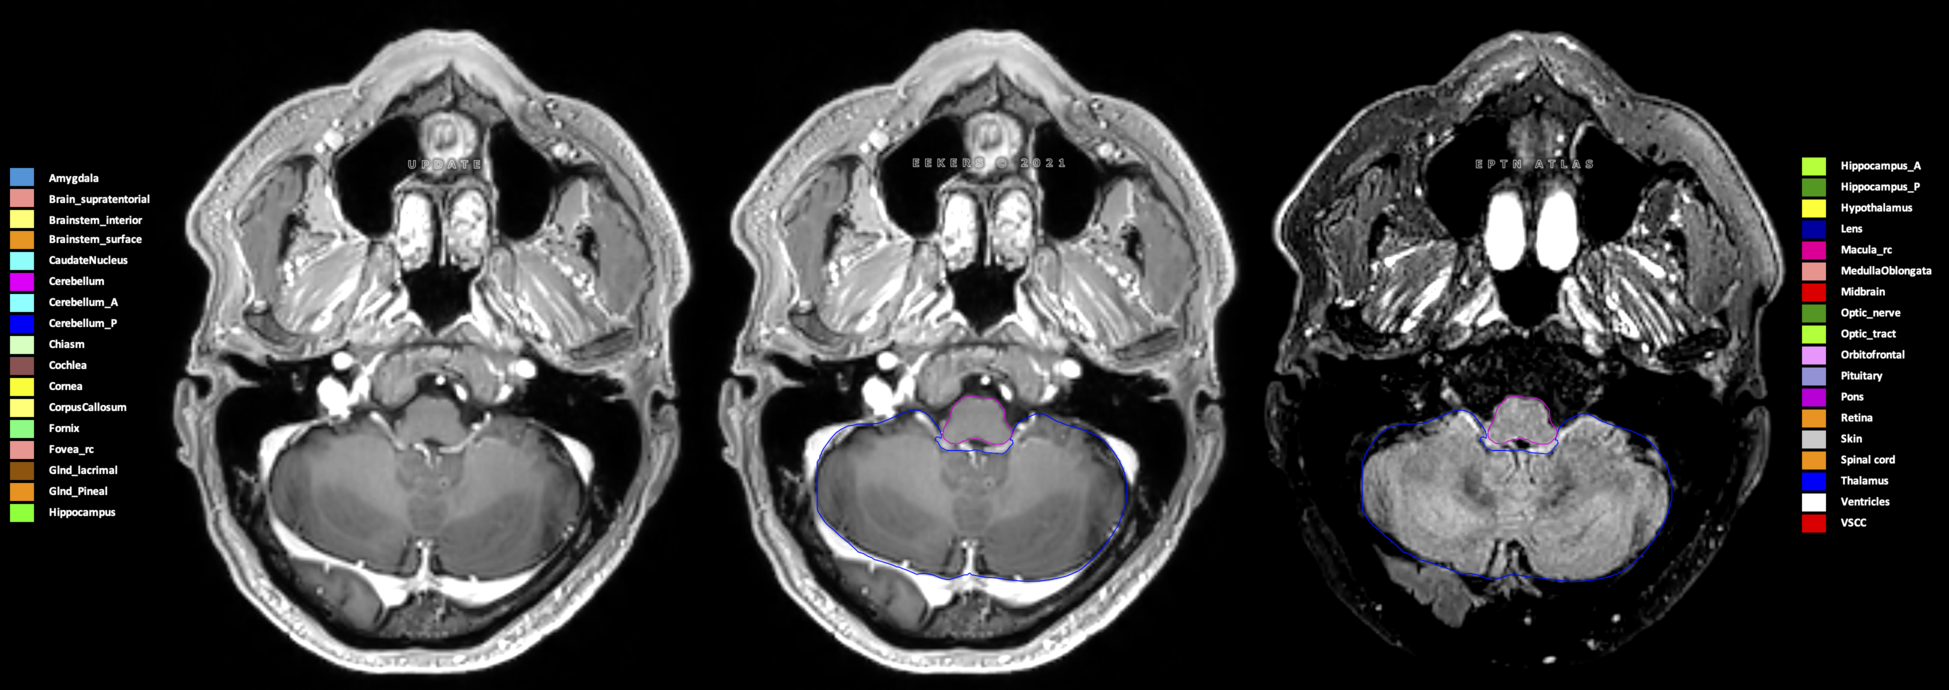

Eekers et al. have published an international neurological atlas for contouring of organs at risk in consensus with the European Particle Therapy Network (EPTN) in 2018 and an update in 2021. The purpose of this consensus atlas is to decrease inter- and intra-observer variability in delineating OARs relevant for neuro-oncology.

Included are all OARs known to be relevant for radiation-induced toxicity in neuro-oncology: brain, brainstem (midbrain, pons, medulla oblongata), chiasm, cerebellum (anterior & posterior), cochlea, cornea, hippocampus (anterior & posterior), hypothalamus, lens, lacrimal gland, optic nerve, pituitary, skin, and vestibular & semicircular canals. To further facilitate research on cognition, vision and radiological changes after irradiation of the brain, potential clinically-relevant OARs are included: amygdala, caudate nucleus, cerebellum (anterior & posterior), corpus callosum, fornix, macula, optic tract, orbitofrontal cortex, periventricular space (PVS), pineal gland, and thalamus.

Three-dimensional delineation of the 25 consensus OARs for neuro-oncology are shown on CT (WW/WL 120/40, 3000/600), 3T MR images, (T1Gd, T2FLAIR 1mm) and 7T MR (MP2RAGE 0.7 mm). All are presented in transversal, sagittal and coronal view.